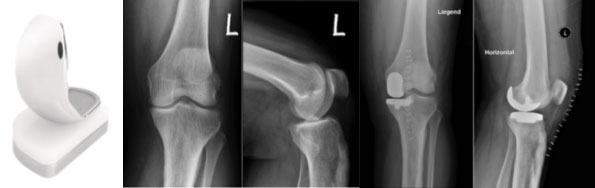

Unikondyläre Knieprothese / Oberflächenersatz Firma Mathys (BalanSys) und Beispiel einer entsprechenden prä- und postoperativen Bildgebung